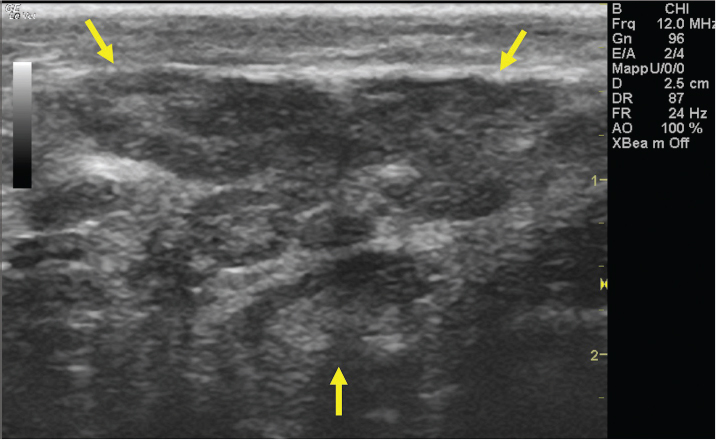

The left jugular vein appeared as an anechoic tubular structure which collapsed under the probe pressure, the color Doppler examination revealed normal blood flow within the vessel (Fig. 3). Bi-dimensional ultrasonography of the right jugular vein showed a heterogeneous, non-cavitating, hypoechoic structure occluding a narrowed right jugular vein for about 30 cm of length localized in the proximal and mid-portion of the neck compatible with a thrombus (Fig. 4). The color Doppler examination showed blood flow through the lateral portions of the thrombus in the cranial and mid-portions of the right jugular vein (Fig. 5). Cranially to the thrombus, a marked distension of the maxillary and linguofacial veins was evident, with a turbulent and echogenic flow; the latter was compatible with blood stasis near the thrombus (Fig. 6). Caudally to the thrombus, the right jugular vein presented reduced diameter, thickened walls, and normal blood flow (Fig. 7). The cranial part of the thrombus originated from a heterogeneous scare tissue, localized at the level of the right mandibular angle (Fig. 8). After injection of the first saline contrast bolus in a right facial vein, no microbubbles appeared in the right jugular vein, caudally to the thrombus, proving the presence of a complete right jugular vein occlusion. On the contrary, after injection of the second bolus, microbubbles were visualized in the left jugular vein as small, intense, echo signals within the vein lumen, demonstrating the presence of collateral circulation that drained the blood from the right facial veins to the left jugular vein (Fig. 9). Venography results confirmed the complete occlusion of the right jugular vein and the presence of submandibular venous collaterals that connected the right facial veins with the left jugular vein (Figs. 10 and 11). Based on the previous results, the diagnosis of JVT with complete occlusion of the vessel lumen was confirmed. The horse’s owner refused any proposed medical or surgical therapy.

Fig. 4. Bi-dimensional ultrasonographic image of the right jugular vein in longitudinal section. The lumen of the vessel was occluded by a heterogeneous, non-cavitating, hypoechoic structure compatible with a thrombus (arrows).ç